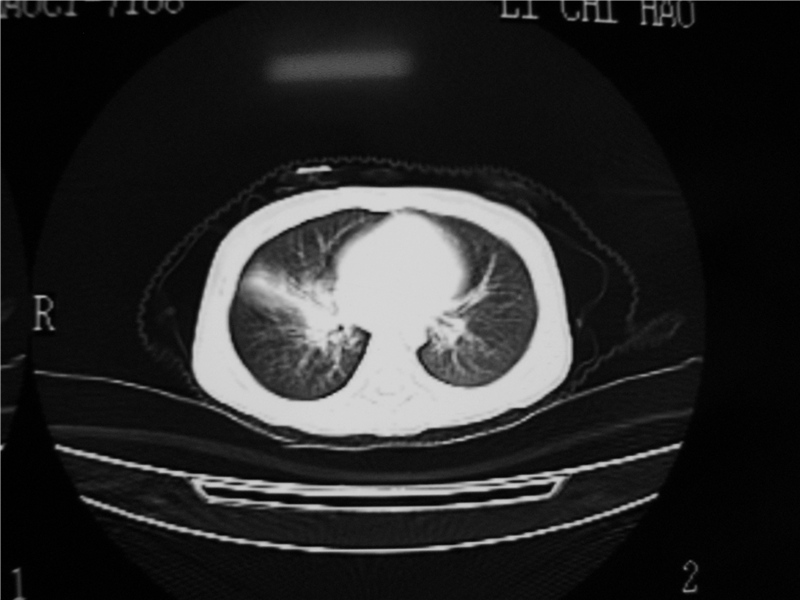

标题: PED3236:男2岁进食花生米后发烧10天。

右肺中叶及下叶内段大片实变密度增高影,可见支气管气象,肺炎.

摄吸气及呼气相对比片,本例为有肺中叶阻塞性炎症、不张,右肺下叶阻塞性炎症。

1)右肺炎症并右肺中叶肺不张,右肺上叶充气不良。2)右侧支气管异物不排除。

结合临床考虑支气管异物并阻塞性肺炎、肺不张。